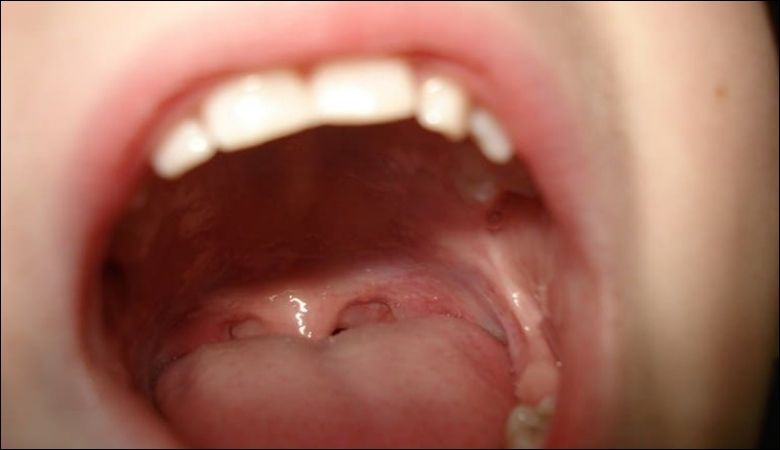

Nổi hạt ở cuống lưỡi là tình trạng phổ biến khiến nhiều người lo lắng, đặc biệt khi kèm theo cảm giác khó chịu hoặc đau. Hình ảnh nổi hạt ở cuống lưỡi thường cho thấy các nốt sần nhỏ, có thể do nhiều nguyên nhân từ lành tính đến cần chú ý y tế.

Hình ảnh nổi hạt ở cuống lưỡi và các triệu chứng kèm theo

Hình ảnh nổi hạt ở cuống lưỡi thường cho thấy các nốt nhỏ màu đỏ, trắng hoặc hồng, tập trung ở phần cuống lưỡi. Triệu chứng nổi hạt ở cuống lưỡi có thể bao gồm cảm giác ngứa, đau nhẹ hoặc khó chịu khi ăn uống.

Trong một số trường hợp, người bệnh có thể gặp thêm triệu chứng như sưng lưỡi, hơi thở có mùi hoặc khó nuốt. Nếu các triệu chứng này kéo dài, bạn nên thăm khám để xác định nguyên nhân chính xác.